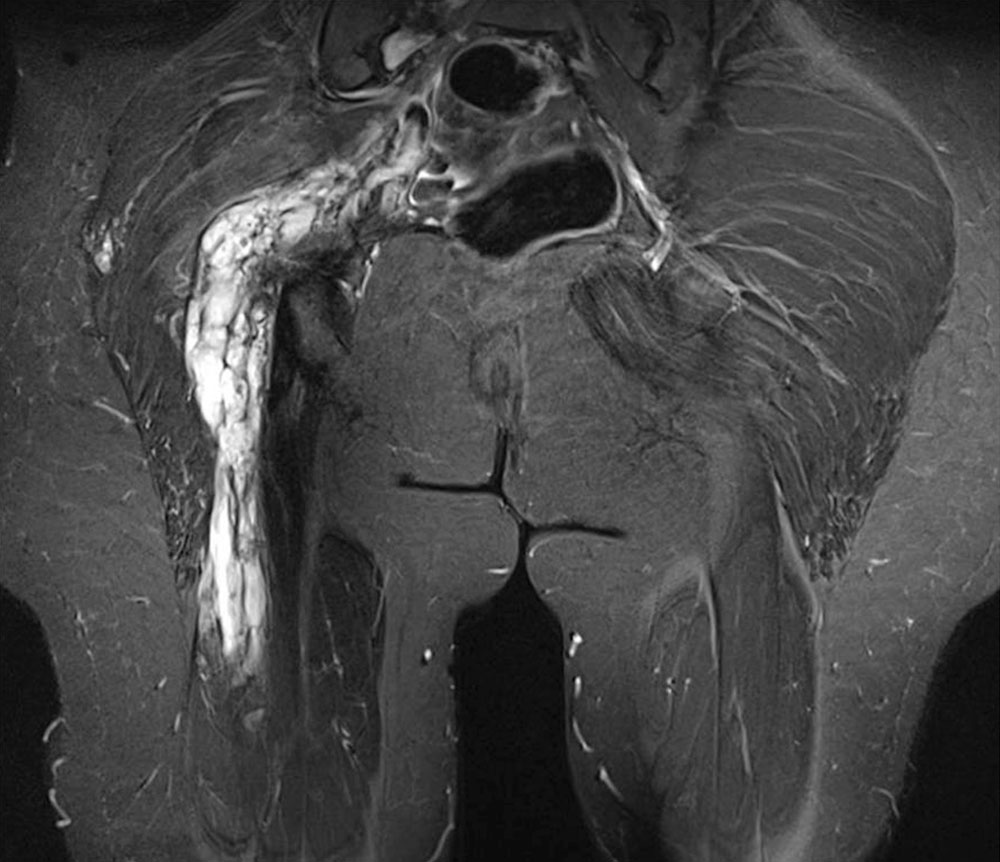

Depending on the volume of the venous malformation, blood congestion occurs because of hydrostatic pressure. Depending on posture, this congestion worsens and triggers troublesome tightness. Since the accumulated blood is also warmer than the surrounding soft tissue, it acts like an “internal radiator”, increasing the discomfort. The location of the malformation also influences the degree of congestion and thus the pain, which is described as dull. Venous malformations of comparable volume are more painful in the legs than in the arms or face because of the higher hydrostatic pressure. Within the subcutis, venous malformations can expand over time and thus are increasingly filled with more blood. Within the muscles, however, the muscle fascia and muscle tone limit the extent of congestion. Larger malformations, which are mainly formed subfascially in the muscles, cause comparatively little pain, especially if they are surrounded by properly developed muscles. On the other hand, smaller subfascial VMs near the knee or on the sole of the foot can cause severe, load-dependent pain.

The very slow blood flow in a venous malformation can lead to circumscribed thrombophlebitis owing to localized intravascular coagulation (LIC), which rarely affects the entire malformation. As a rule, the localized thrombi, which are sonographically detectable as oval, echogenic structures, reach a size of 10–15 mm at most. Nevertheless, phlebitis in a venous malformation can be very painful. There is pain at rest, which is increased by touch and pressure. It is characterized by sudden onset, a stabbing character and regression within a few days associated with palpable hardening. If the connections between the immature vessels and the deep veins are only small in caliber, thrombosis and pulmonary embolism will very rarely occur. Large connections by communicating veins must be occluded, as they present a considerable risk of thrombosis and embolism.